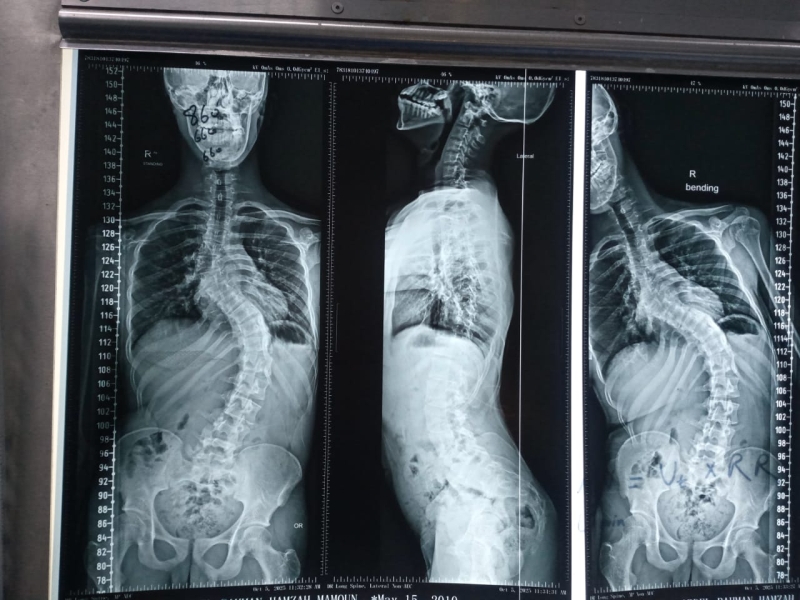

خبرني - شهد قسم جراحة العمود الفقري في مستشفى الأمير حمزة إنجازًا طبيًا مميزًا تمثّل في إجراء تدخّل جراحي معقّد لتصحيح جنف العمود الفقري لدى أحد المرضى الذين يعانون من تشوّه حاد في الفقرات.

وقد أُجريت العملية باستخدام جهاز الملاحة الجراحية المتقدّم، الذي أتاح دقةً عالية في التعامل مع التشوّهات البنيوية الشديدة، وسهّل توجيه الأدوات الجراحية ضمن المسار الآمن والمثالي.

كما اشتملت العملية على إزالة أجزاء محددة من الأطراف الخلفية للفقرات لتحقيق التصحيح المطلوب واستعادة التوازن والمحاذاة الطبيعية للعمود الفقري.

وتم تنفيذ هذا الإجراء الدقيق تحت نظام مراقبة الأعصاب المتواصل (Intraoperative Neuromonitoring) لضمان سلامة الوظائف العصبية طوال مراحل العملية.